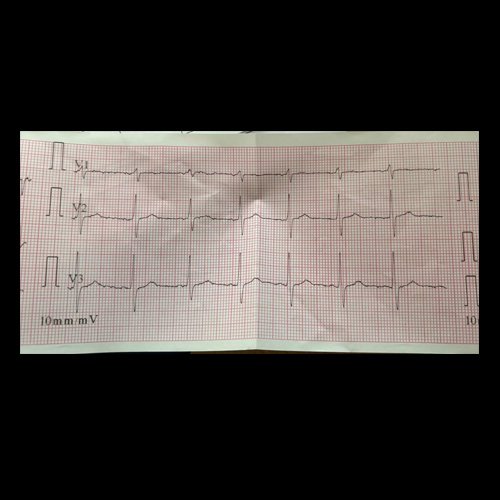

• Electrocardiograma 12 derivaciones (Día 0): ritmo regular y sinusal, FC 85 lpm, eje cardíaco conservado. Sin signos de isquemia aguda ni sobrecarga.

Electrocardiograma DÍA 0